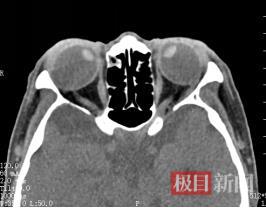

李婆婆患超高度近视已数十年。近年间,其双眼固视于内下方,右眼近乎完全内陷,右眼视觉功能完全丧失,左眼仅残存鼻侧少许视野。严重的视觉障碍致使其生活无法自理,显著影响其容貌外观,给她造成生理和心理的双重打击。她辗转求诊于多家医院,均未获有效治疗,后又前往武汉大学人民医院眼科中心眼Ⅳ科寻求救治。

经周炼红教授细致检查,李婆婆被诊断为“高度近视性固定性内斜视”,也被称为“重眼综合征”。因其近视度数超过2000,造成眼球异常增长,眼球后极部进行性膨隆突破肌圆锥,导致眼外肌解剖关系紊乱和力学失衡。严重的后巩膜葡萄肿显著增加手术难度,术中稍有不慎就可能造成眼外肌断裂,甚至巩膜破裂或球后暴发性出血,导致失明甚至眼球萎缩等严重风险。